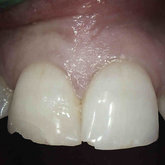

He received his Diploma in Implantology in 2016 from the University of Pretoria, which he passed with Distinction. He is also a member of the International Team for Implantology (ITI), which is based in Switzerland and offers members access to the latest research and cutting-edge techniques.

Porcelain crowns and restorations made in one appointment.

We make it a priority to incorporate the latest in dental technology in everything we do at our practice. ...